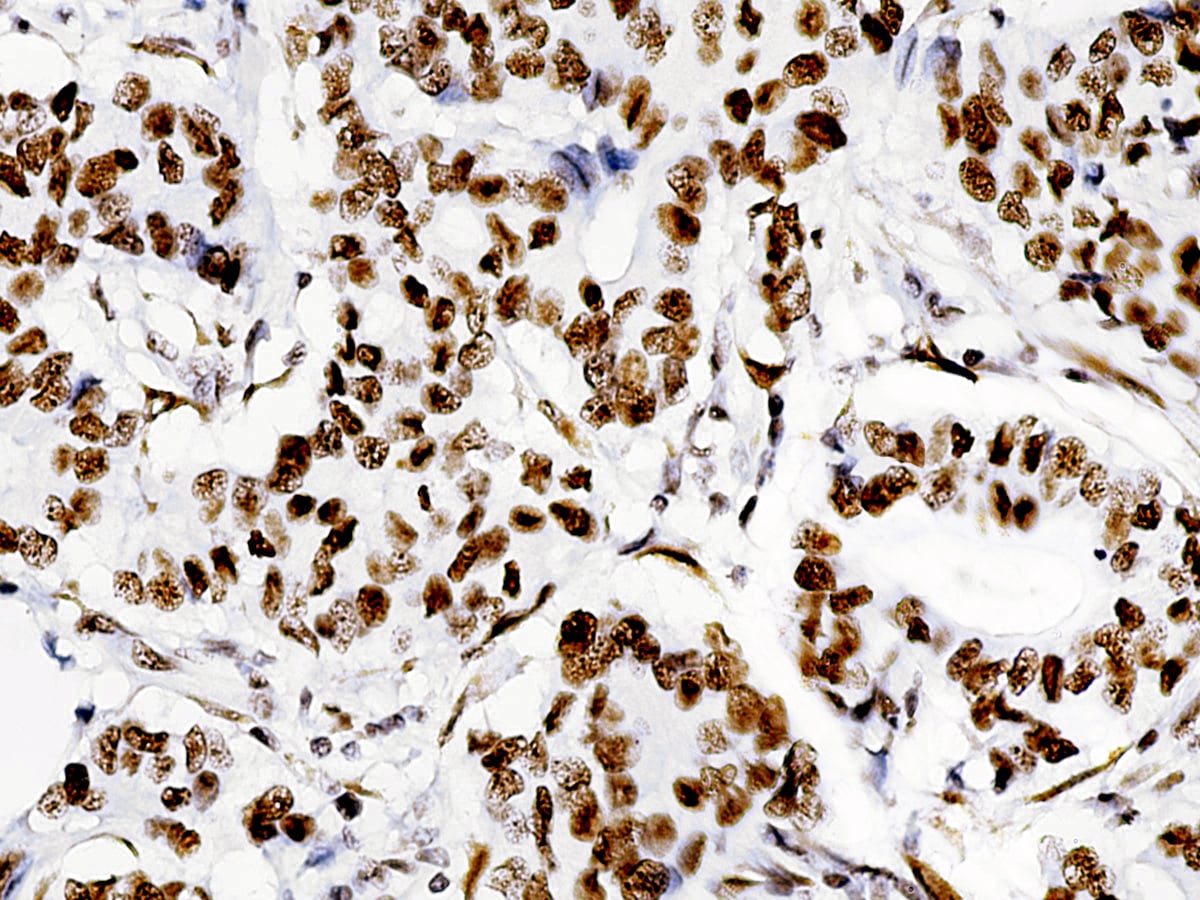

Anti-ATRX, Clone D-5

| Tissue Type/Cancer Type | Breast carcinoma |